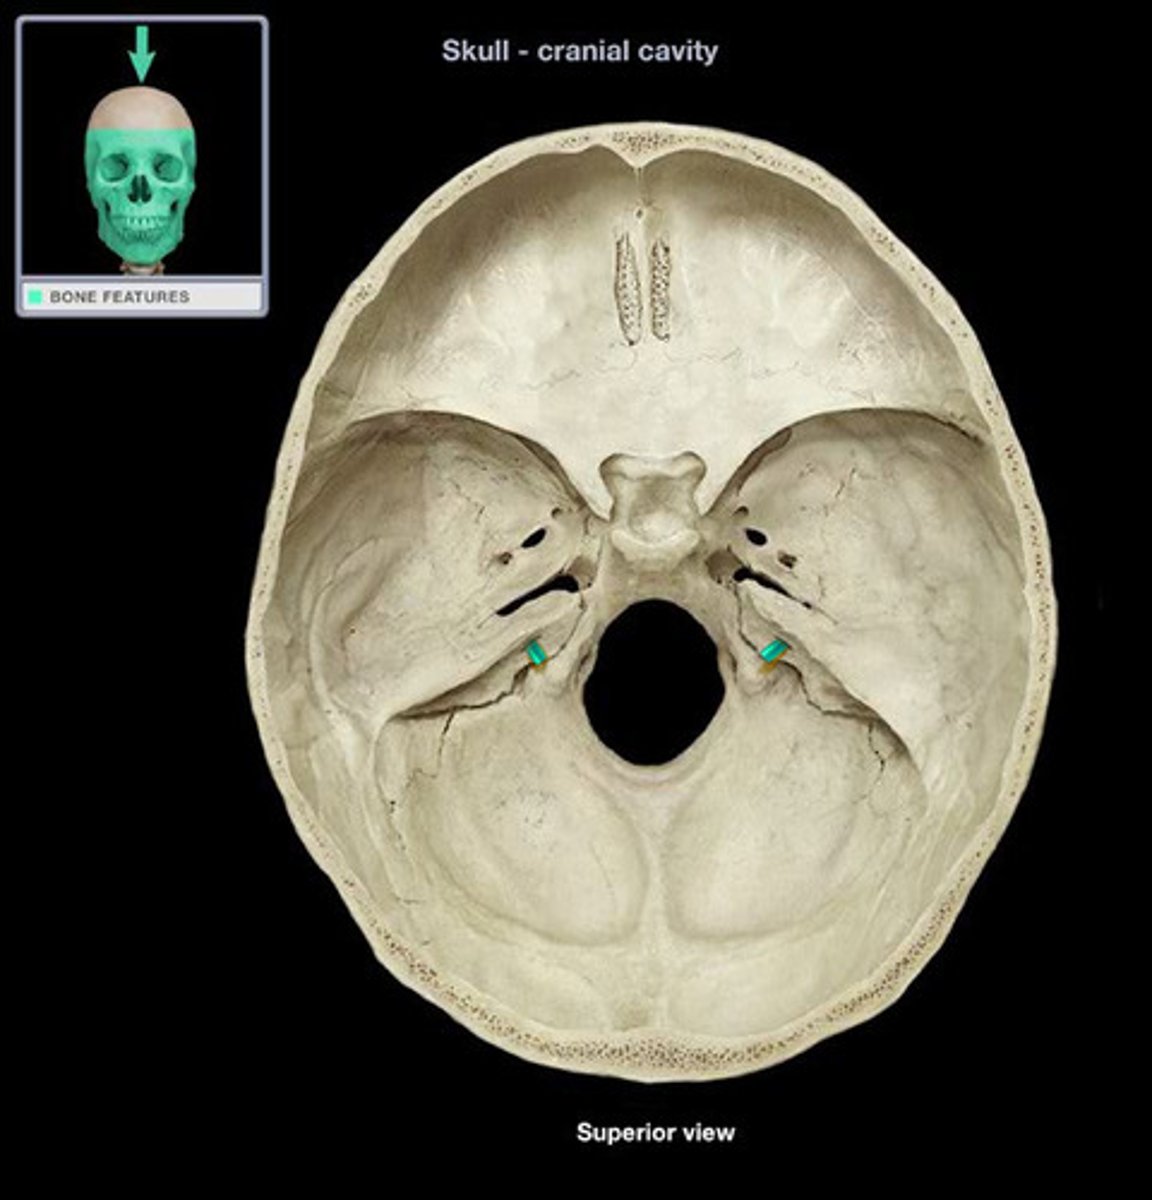

1. occipital

2. temporal (petrous part)

3. sphenoid (posterior)

what 3 bones make up the posterior cranial fossa?

foramen magnum

large opening at the based of the skull that transmits the spinal cord, vertebral arteries, and spinal accessory nerve (CN XI)

jugular foramen

opening that transmits the internal jugular vein and cranial nerves IX, X, and XI

hypoglossal canal

hole that transmits the hypoglossal nerve (CN XII)